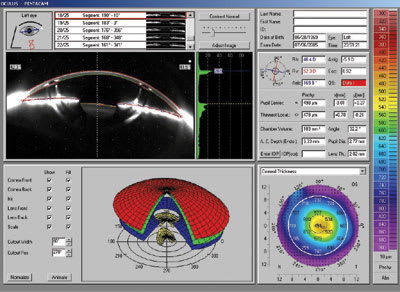

Figure 3 shows the change in MH's post ortho-k higher-order aberrations

before the instillation of Alphagan P (top display) and 30 minutes after (lower

display). It's clear that a dramatic reduction in spherical aberration as well as

most other higher-order aberrations has occurred. Subsequently, MH reported a dramatic

reduction in nighttime symptoms.

Figure 3.

Higher-order aberrations |